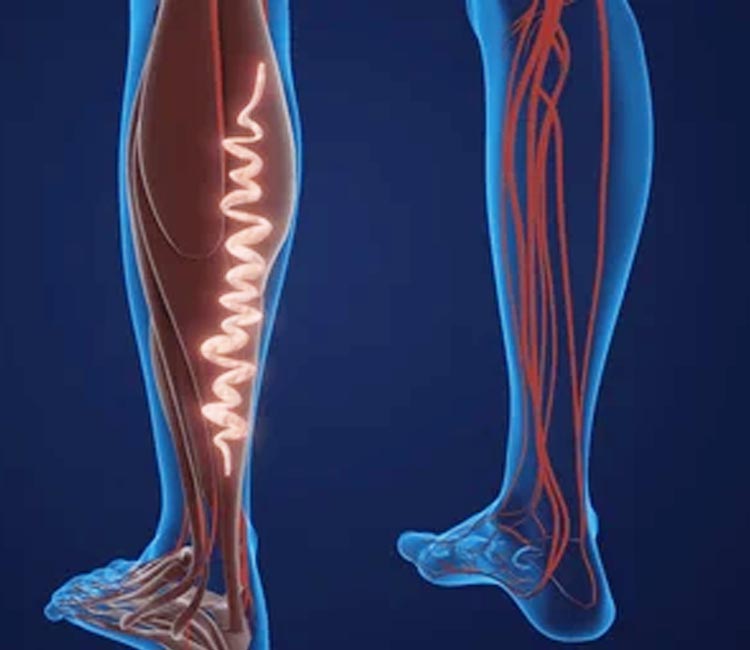

We offer cutting-edge treatments for varicose veins, using advanced surgical techniques to alleviate pain, enhance circulation, and restore the natural look and function of your legs.